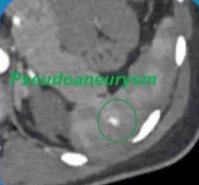

- 多发性损伤 CT 显示撕裂 没有 造影剂外溢 |

远端栓塞 |

伴有血管损伤的患者 |

特定受损血管的选择(超选择行) |

选择性栓塞 |

增加操作时间和更大的脾梗塞 |

弹簧栓子和栓塞微粒 |

脾梗死或脾脓肿形成 |